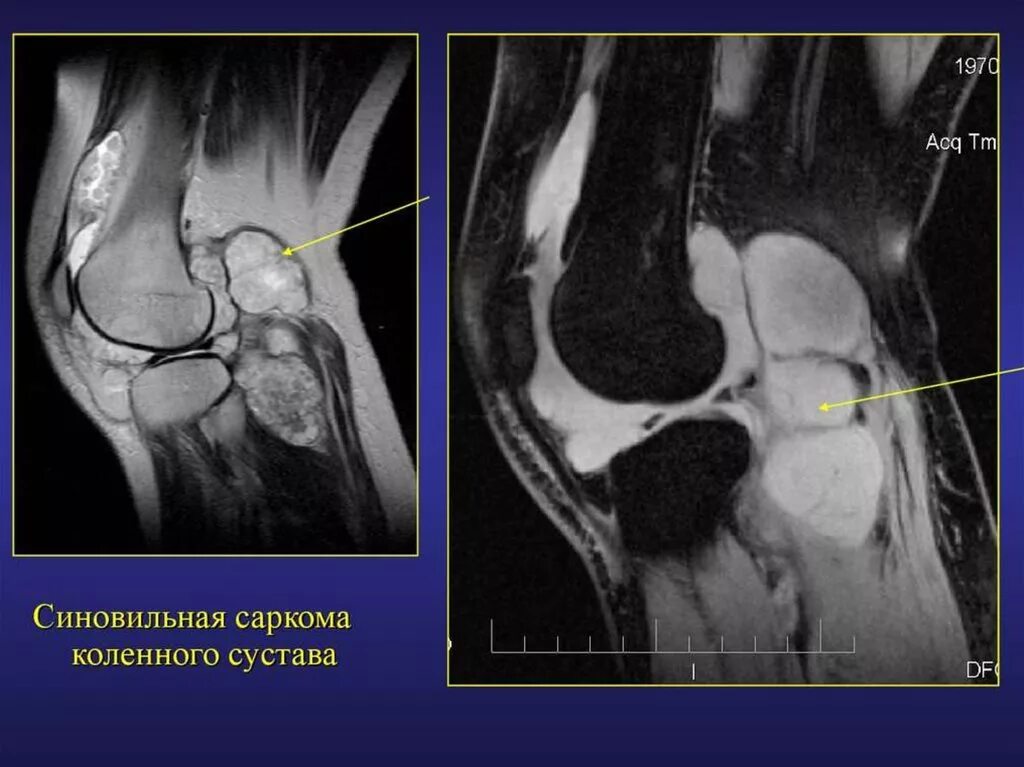

Саркома мрт